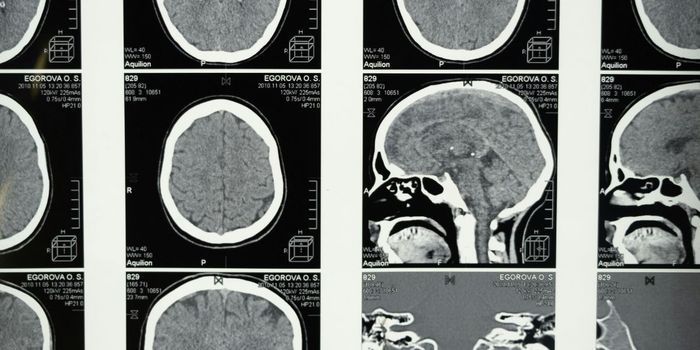

JAN 08, 2025Clinical & Molecular DXLissencephaly refers to a rare condition in which the folds usually found in the brain do not develop, and brain develop ...

JAN 03, 2025Clinical & Molecular DXDetecting changes in the brain can be very difficult. Scientists have now developed a kind of molecular flashlight that ...

DEC 17, 2024Clinical & Molecular DXDeep learning is a computational tool that is a subset of Artificial Intelligence (AI), and these technologies are often ...

DEC 03, 2024Clinical & Molecular DXMRI (magnetic resonance imaging) is an incredible technique that was developed in the 1980s. It uses radio waves, giant ...